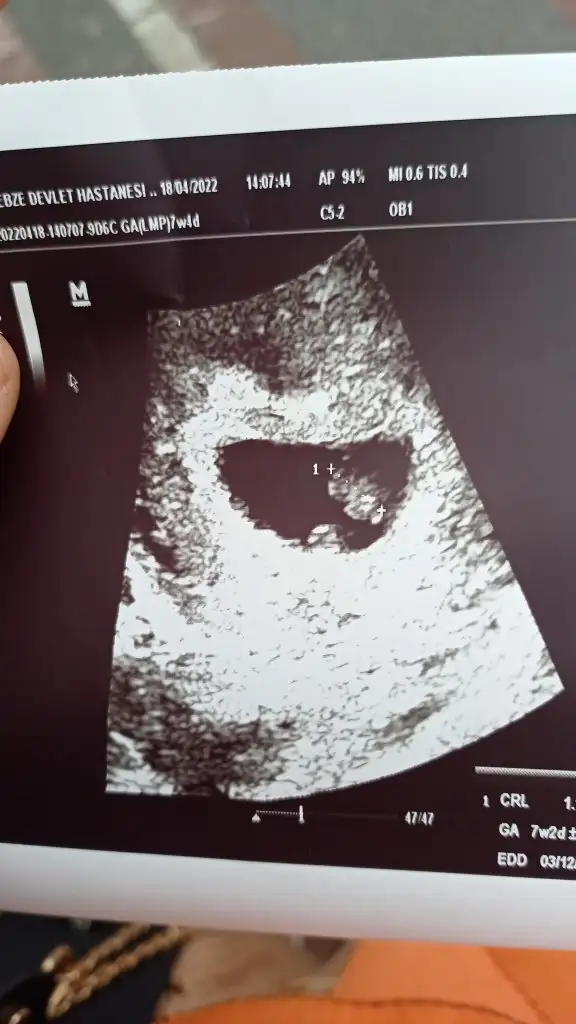

8+4 haftalik bu goruntulerdi karindan, erkek demistiniz😊

Ramziye göre bakmıştım solda olunca erkek olabilir dedim ama ramzi en fazla 8 e kadar bakılır yazıyor şimdi ramzi değil kese duruş ile bakarsak bu görüntü de prenses diyor 🙏 Sen ne hissediyorsın